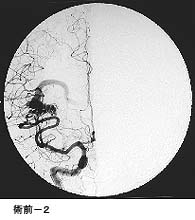

脳動静脈奇形に対する液体塞栓物質を用いた治療

治療により異常血管は閉塞されました。